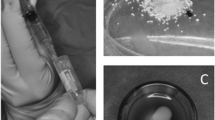

To compare the osteogenic effects of rBMSC secretome, hFMSC secretome, and hAMSC secretome on the osteogenic differentiation of rBMSCs, ALP and Alizarin Red S staining were performed. The results showed that both rat and human secretome could induce osteogenic differentiation of rBMSCs. Furthermore, the hFMSC secretome demonstrated the strongest osteogenic induction ability (Fig. 1a, b).

Secretome from human fetal mesenchymal stem cells (hFMSCs) had more osteogenic potential and lower immunogenicity than that from rat bone marrow-derived mesenchymal stem cells (r BMSCs) and human adult mesenchymal stem cells (hAMSCs), as well as no effect on cell viability. a Both the alkaline phosphatase (ALP) staining and Alizarin Red S staining showed that more calcium deposits could be found after hFMSC secretome treatment. b The semi-quantitative results of Alizarin Red S staining demonstrated that significantly more mineralization was seen in the hFMSC secretome group. c Immunogenicity was determined by mixed rat peripheral blood lymphocyte reaction. The hFMSC secretome had no significant effect on rat peripheral blood lymphocyte proliferation. d Significant lymphocyte proliferation was stimulated after administration of hAMSC secretome. e Cell viability was evaluated by the MTT assay. The optical density (OD) level of rBMSCs treated with hFMSC secretome showed no significant difference among the doses from 10 μg/μl to 200 μg/μl. *p < 0.05, **p < 0.01. d days

Different doses of hFMSC secretome had no effect on cell viability but promoted osteogenic differentiation of rBMSCs

To investigate the effect of hFMSC secretome on cell viability, the MTT assay was performed. The results showed that there was no significant difference among the five groups with different doses of secretome (excluding the dose of 0) during 48- and 72-h culture (Fig. 1e). To clarify the effect of different doses of hFMSC secretome on osteogenesis of rBMSCs in vitro, ALP and Alizarin Red S staining were performed at day 3, and days 7 and 14, respectively. The expression of alkaline phosphatase and the amount of calcium deposits were remarkably increased in the group with a dose of 100 μg/μl. The quantitative results showed that hFMSC secretome at a dose of 100 μg/μl could significantly increase calcium nodule formation compared to other doses (Fig. 2). Furthermore, the real time PCR results demonstrated a remarkable increase in the expression of Runx2, OCN, OPN, and Osx in the secretome group with the dose of 100 μg/μl at days 3 and 10. The ALP in the secretome group was significantly upregulated at day 3, but showed no significant difference at day 10 (Fig. 3).